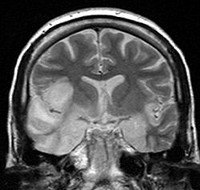

A83.3 Энцефалит Сент-Луис